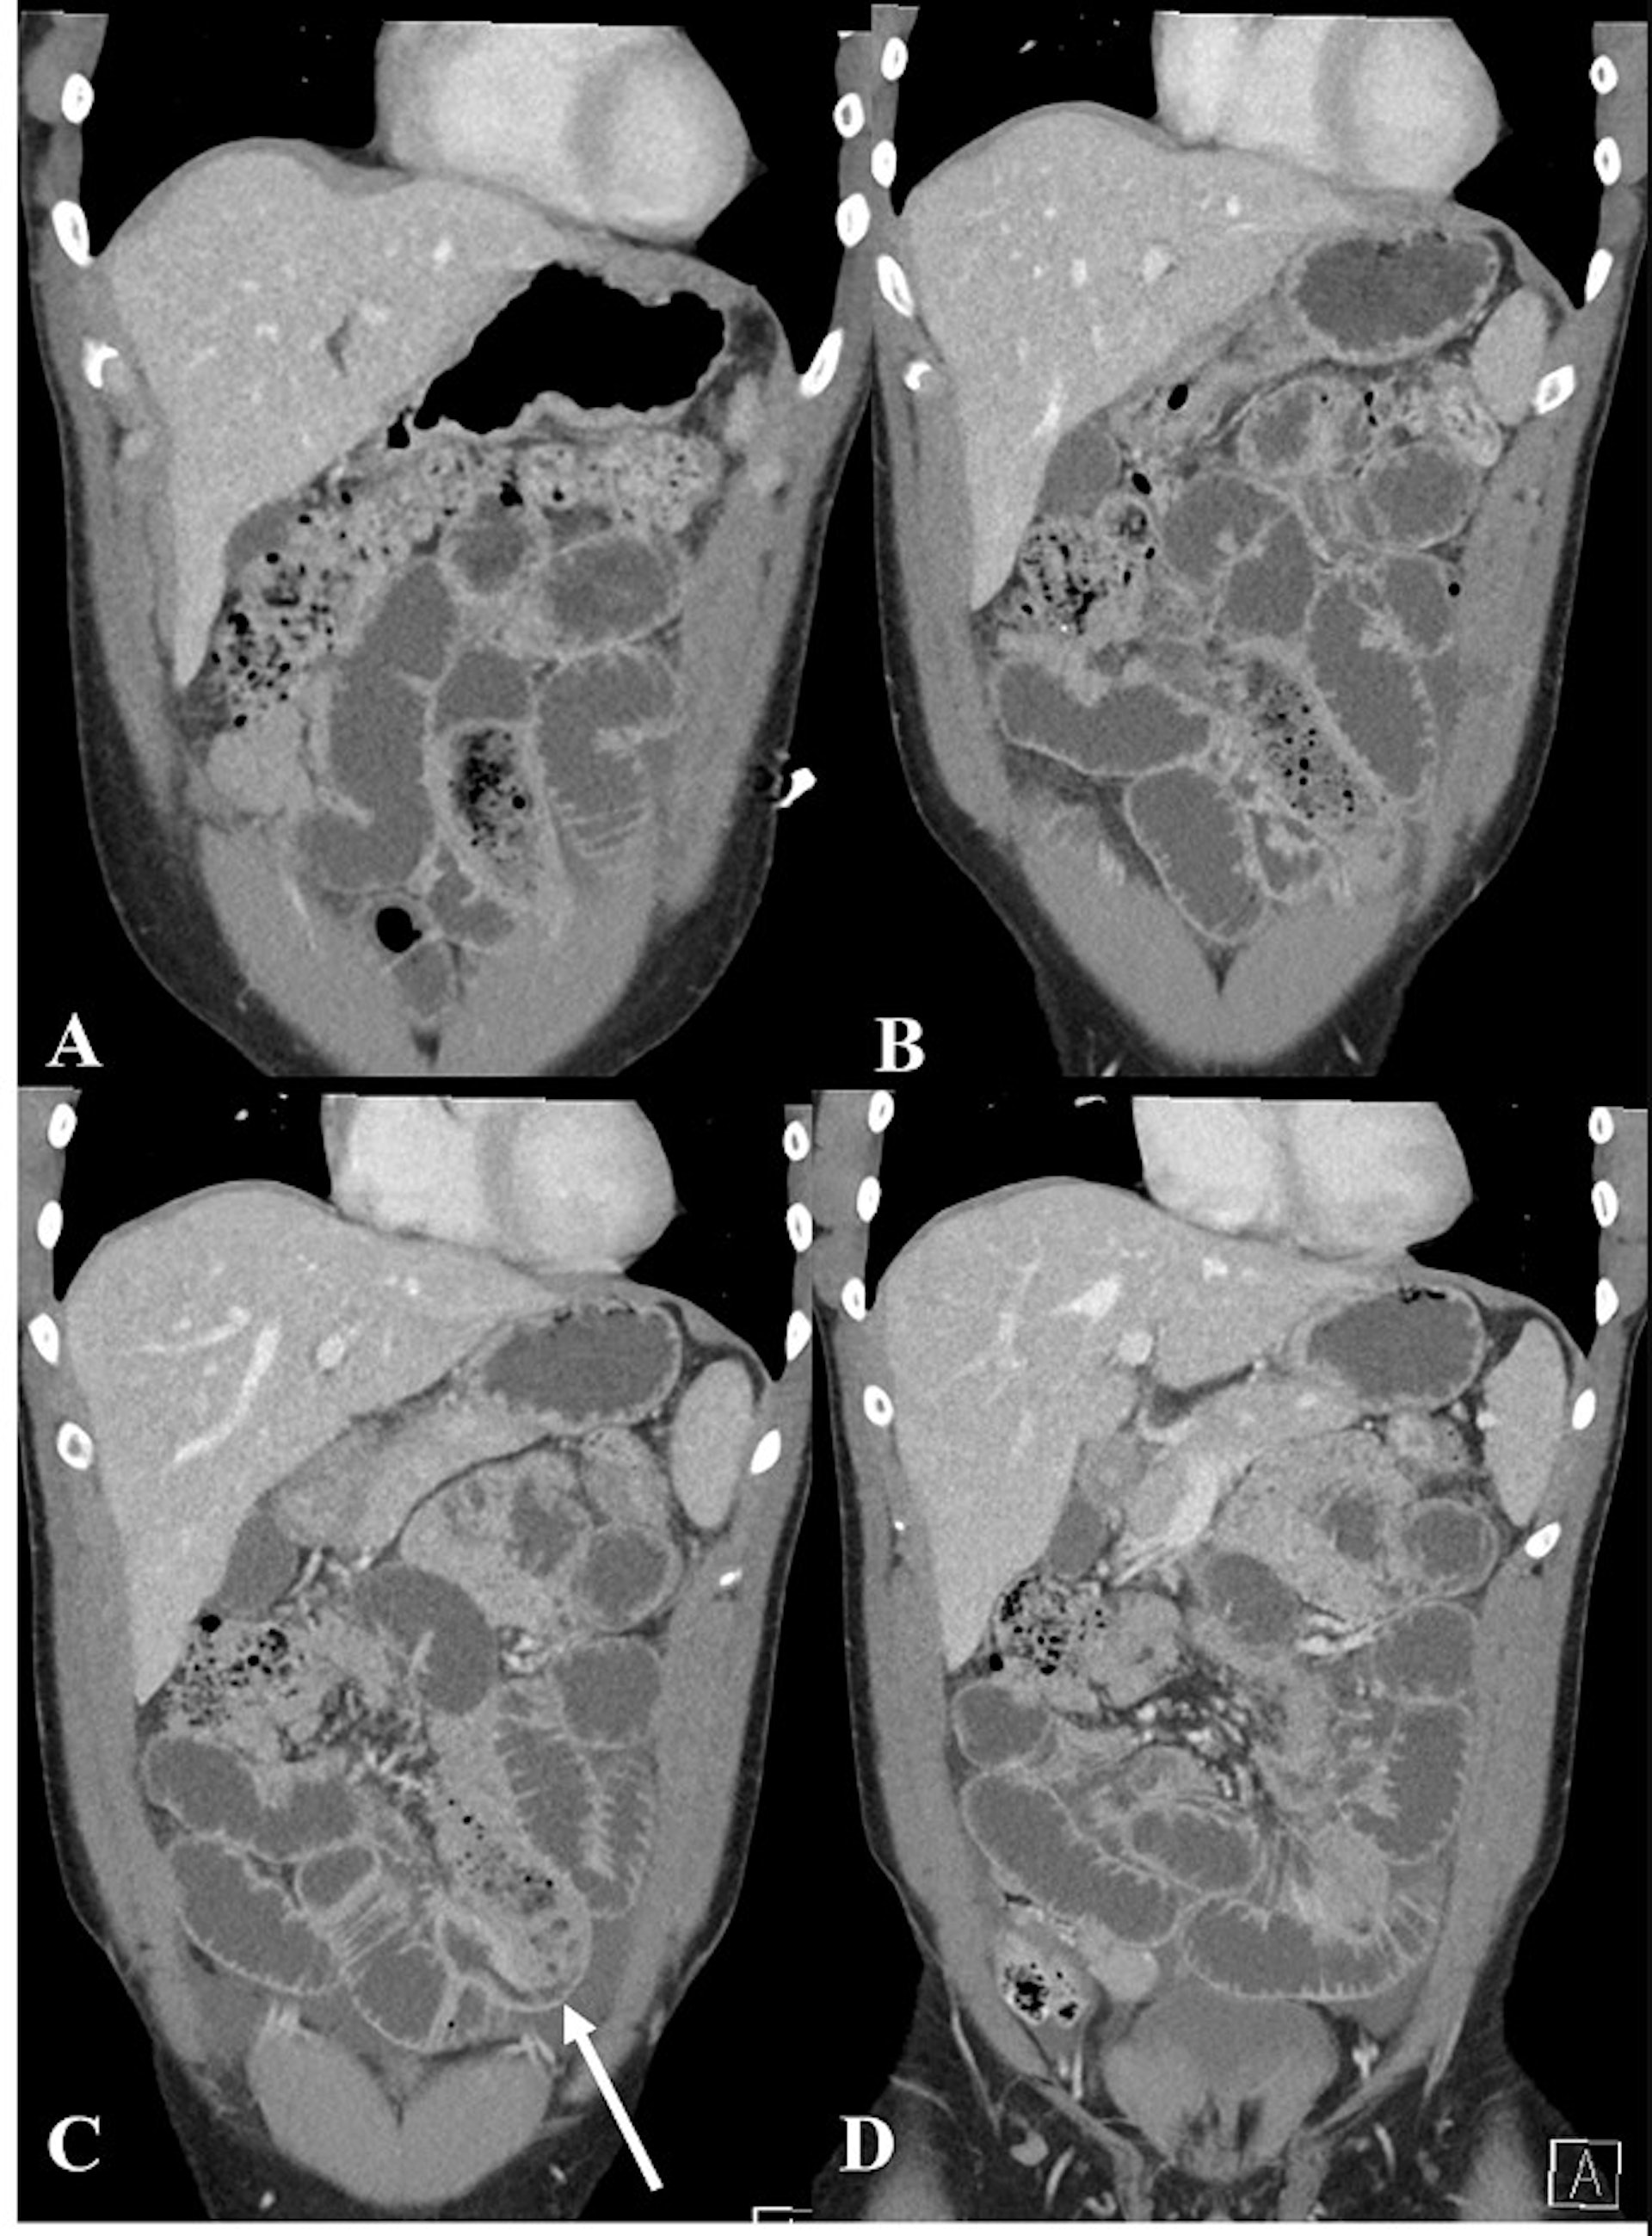

醫生為男子進行電腦斷層掃瞄,顯示他的腸內有明顯的長條狀異物。(「Cureus」圖片)

醫生為男子進行電腦斷層掃瞄,顯示他的腸內有明顯的長條狀異物,而小腸擴張達3.5 cm並伴有糞便。考慮到男子小腸梗阻的嚴重程度,醫生不採取保守治療等待排出,而是緊急透過手術取出異物。從術後拍攝的照片可見,香蕉已經發黑軟爛滲液,而安全套被打了結因此內容物沒有流出。